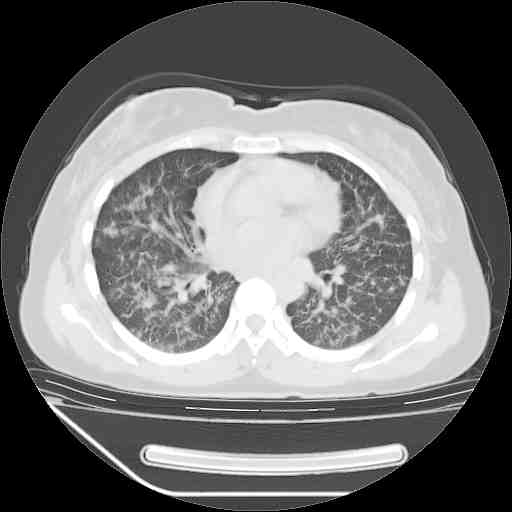

下面是今天刚刚做的,在上海治疗,吃了家属也说不清的一种药,一个月1万左右,

考虑  腺癌肺内转移,治疗较前病灶缩小、减少

肺癌并肺内转移,这种疾病治疗后在影像上看略有好转,不是很显著,但是肿瘤治疗效果影像只是一方面。

支持肺癌并肺内淋巴管炎,  原发灶小了,但转移较前片明显了.

支持右肺下叶周围型肺癌并肺内淋巴管炎,  原发灶小了,但转移较前片明显了.。

标准的细支气管肺泡癌呀!治疗后病情有所控制,也没治愈的迹象!